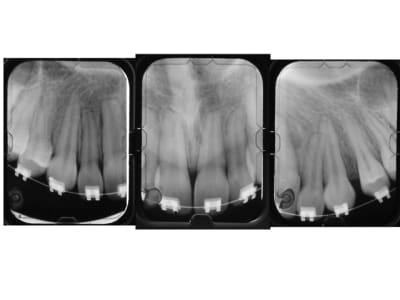

Jeune femme de 53 ans, avant et 2 ans après la fin du traitement. Résultat : résorptions apicales sur 12, 11 et 22.

A noter que cette dernière était carrément sortie de l'os. La 21 par contre ne paraît pas atteinte.

La question que je me pose ici est la suivante : est-ce que c'est la traitement radiculaire qui l'a prévenue, ou est-ce la moindre résistance osseuse liée à la lésion périapicale préexistante ?

Tu peux rajouter celle-là qui va avec, HAIG.

Cette personne a quand même conservé ses dents, malgré que cela déplaise profondément à Ploc qui espère toujours une catastrophe. Qui sait ? elle n'aura peut-être pas lieu...

Pour Dancha, c'est vrai que la dent dépulpée est celle qui a résistée le plus a la résorption.

Tes hypothèses sont bonnes, je suis un ignorant en Histologie mais comme ça une idee.

Est-ce que l'absence du paquet vasculo-nerveux fait que l'action des ostéoclastes est moindre, voir inexistante dans ton cas, il faudrait avoir plusieurs cas avec ce genre de situation pour constater si a chaque fois les dents dépulpées correctement ne se résorbent pas.

Des attelles en U d'Abjean-Genon qu'on voit d'ailleurs sur la pano. Et aussi une petite gouttière supérieure nocturne en protection.

Sur la photo du milieu , il reste pas de la colle sur les canines ?